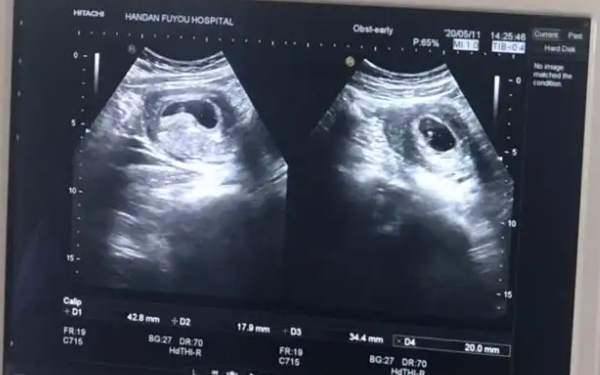

出现胎心胎芽但HCG偏低还是很有可能会出现胎停的,HCG是维持胚胎发育的一个必备因素,母体的HCG水平达不到维持胚胎发育就会出现胚胎停止发育,HCG的值会影响到绒毛的生长旺盛程度,即使胎心胎芽出现,还是容易发生胎停育,影响孩子发育。